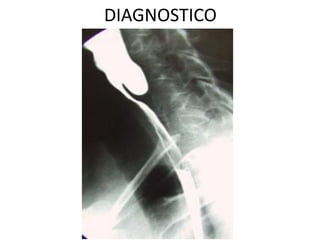

DIAGNOSTICO

1. Esofagograma con bario

• Imagen en:

– “pico de pajaro”

– “punta de lápiz”

• Dilatacion del cuerpo

esofagico